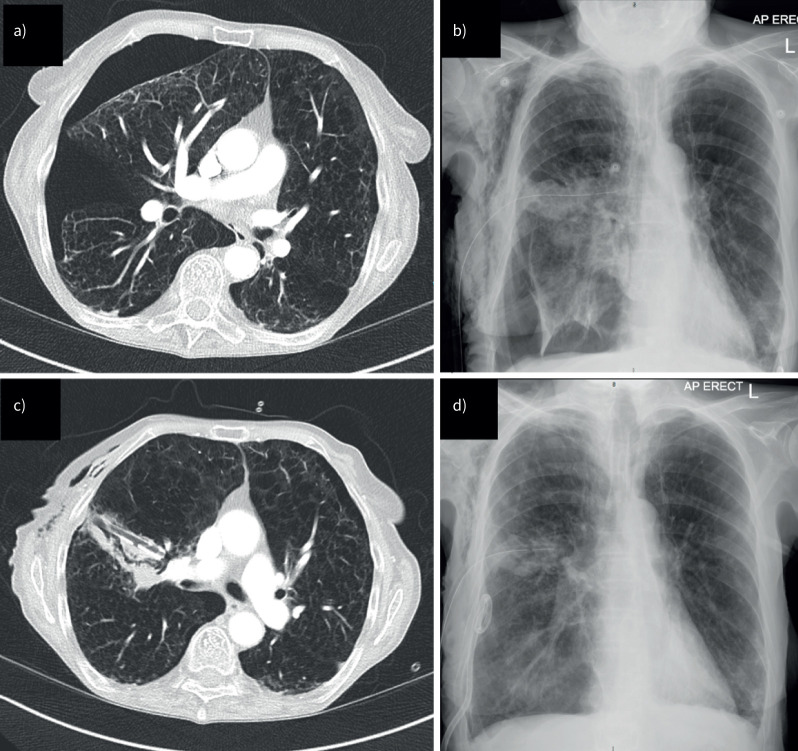

气胸是由肺部气体泄漏到胸膜间隙引起的。如果漏气已经愈合,气胸可能不需要干预,但需要时间来解决。尽管解决了空气泄漏,但根据患者的偏好,程序性管理可能是有保证的。持续的空气泄漏有张力性气胸的风险,需要干预。对于再次发作的气胸或患者因素(如职业风险),应考虑手术预防复发性气胸。这篇综述的目的是描述最近气胸治疗模式向个性化管理转变的证据基础,新指南的支持,以及新型诊断/管理辅助工具(如胸部超声和数字引流系统)的应用。

Pneumothorax arises from pulmonary air leaking into the pleural space. If the air leak has healed, the pneumothorax may not require intervention but will take time to resolve. Procedural management may be warranted, despite resolution of the air leak, depending on patient preference. An ongoing air leak carries a risk of tension pneumothorax and requires intervention. Surgical prevention of recurrent pneumothorax should be considered in cases with a second episode or for patient factors (e.g. occupational risk). This review aims to describe the evidence base for the recent paradigm shift towards individualised management in the treatment of pneumothorax, supported by new guidelines, and the utility of novel diagnostic/management adjuncts such as thoracic ultrasound and digital drainage systems.